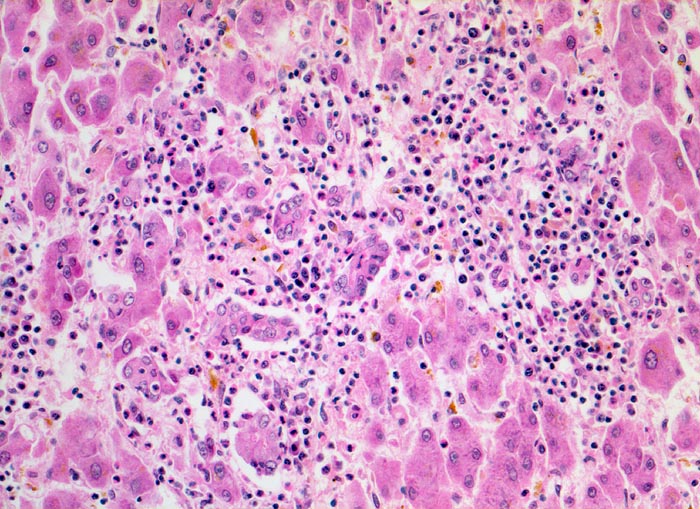

Das histologische Bild der akuten Hepatitis vom Virustyp ist gekennzeichnet durch eine lobuläre Entzündung bei fehlender portaler Fibrose und nur geringer entzündlicher Infiltration der Portalfelder. Es finden sich ballonierte Hepatozyten, Apoptosen (> 1164) und fleckige Nekrosen. Perivenuläre Nekrosen, Brückennekrosen oder konfluierende multilobuläre Nekrosen und eine läppchenzentrale Cholestase können vor allem in klinisch fulminant verlaufenden Fällen nachgewiesen werden. Zahlreiche Makrophagen, welche Diastase-PAS positives Zeroidpigment (> 4319) von phagozytierten nekrotischen Hepatozyten enthalten, zeugen im subakuten Stadium von einer abgelaufenen akuten Hepatitis mit Parenchymnekrosen. Eine Unterscheidung der verschiedenen Typen der viralen Hepatitis und einiger Formen medikamentöser Hepatitiden gelingt rein morphologisch aufgrund des unspezifischen Bildes meist nicht. Für eine ätiologische Klassifizierung sind zusätzliche klinische Angaben erforderlich (Anamnese, Medikamente, Serologie).

Morphologische Merkmale:

• Regelrechte Läppchenarchitektur.

• Lobuläre gemischte Entzündung.

• Ansammlungen zeroidbeladener Makrophagen innerhalb von Parenchymnekrosen (abgebaute fleckförmige Nekrose).

• Apoptosen (hypereosinophile abgerundete Leberzellen).

• Portale gemischte Entzündung.

• Fehlende Fibrose.